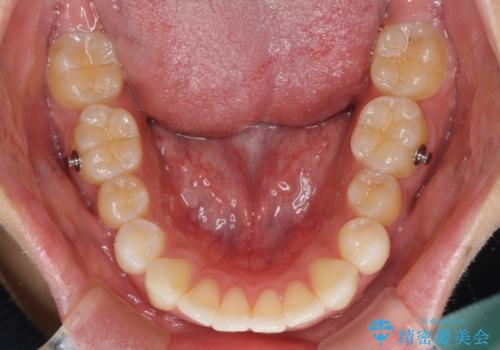

八重歯と奥歯のクロスバイト 上顎骨を拡大してインビザラインで矯正

- インビザライン

- 2年10ヶ月

上顎骨の幅が狭く、奥歯がクロスバイトとなっていたため、急速拡大装置を用いて上顎骨を側方拡大し、八重歯を収めるスペースを獲得しつつクロスバイトを改善することとしました。

上顎骨を思い通りに拡大できたため、当初の計画通りに非抜歯矯正で仕上げることができました。